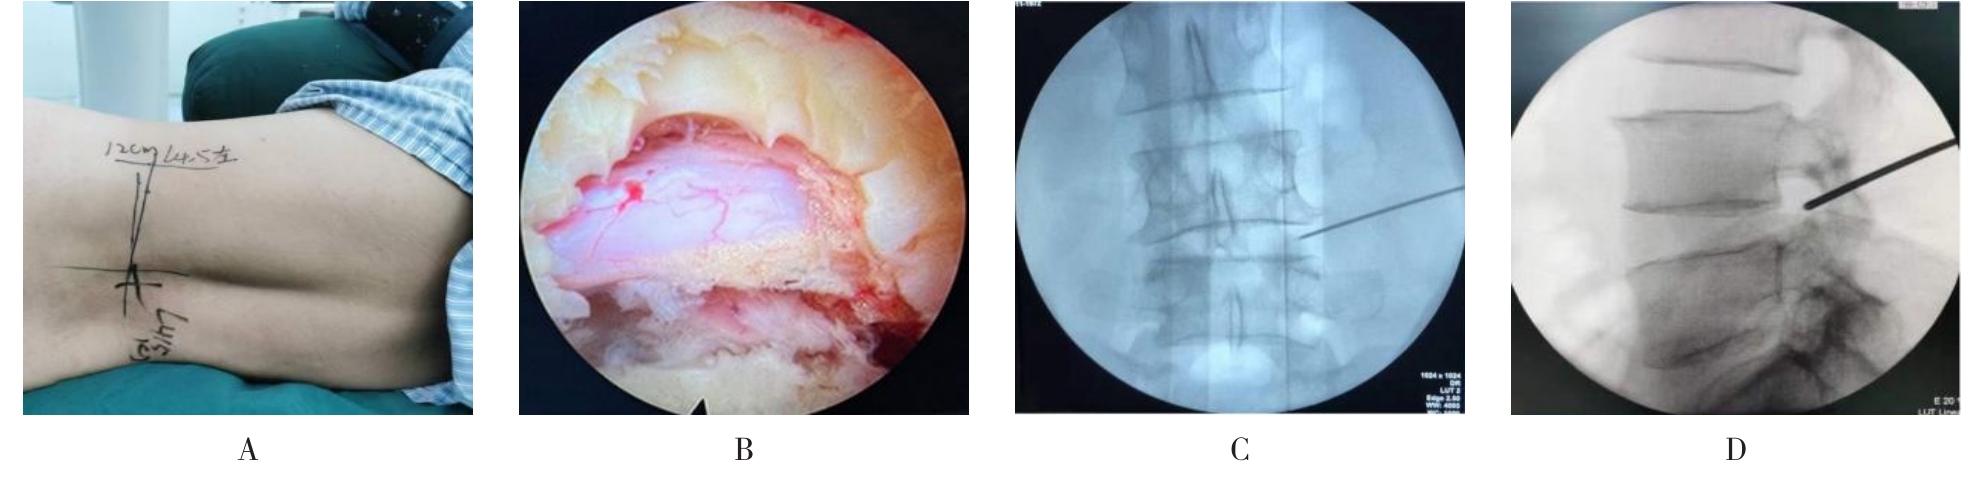

• 不同入路脊柱内镜手术治疗L4/5节段脱垂型腰椎间盘突出症的疗效比较

摘要:目的 观察经椎间孔入路内镜下腰椎间盘切除术(TELD)和经椎板间入路内镜下腰椎间盘摘除术(IELD)治疗L4/5节段脱垂型腰椎间盘突出症(LDH)的临床疗效。方法 回顾性分析2020年11月-2022年11月该院采用脊柱内镜手术治疗的75例L4/5节段脱垂型LDH患者的临床资料。根据手术入路的不同,将患者分为TELD组(53例)和IELD组(22例)。比较两组患者的手术情况和术后疗效。结果 与TELD组比较,IELD组的手术时间明显缩短,术中透视次数明显减少,差异均有统计学意义(P < 0.05);两组患者住院时间和并发症发生率比较,差异均无统计学意义(P > 0.05)。所有患者术后均获得12~19个月的随访。两组患者末次随访时的视觉模拟评分法(VAS)评分和Oswestry功能障碍指数(ODI)明显低于术前,且IELD组明显低于TELD组,差异均有统计学意义(P < 0.05)。按照突出物和神经根的不同位置进一步分析,两组肩上型患者(TELD组10例,IELD组6例)末次随访时的VAS评分和ODI明显低于术前,且IELD组末次随访时的VAS评分明显低于TELD组,差异均有统计学意义(P < 0.05);两组腋下型患者(TELD组8例,IELD组16例)末次随访时的VAS评分和ODI明显低于术前,且IELD组明显低于TELD组,差异均有统计学意义(P < 0.05);35例肩前型患者经TELD术后,末次随访时的VAS评分和ODI明显低于术前,差异有统计学意义(P < 0.05)。按照突出物的不同Lee分区进一步分析,两组Lee Ⅲ区患者(TELD组44例,IELD组10例)末次随访时的VAS评分和ODI明显低于术前,且IELD组的ODI明显低于TELD组,差异均有统计学意义(P < 0.05);两组Lee Ⅳ区患者(TELD组9例,IELD组12例)末次随访时的VAS评分和ODI明显低于术前,且IELD组明显低于TELD组,差异均有统计学意义(P < 0.05)。结论 采用TELD和IELD治疗L4/5节段脱垂型LDH,均可获得较满意的减压效果,但IELD的手术时间相对较短,X线透视次数较少,且对肩上型、腋下型、Lee Ⅲ区和Lee Ⅳ区的减压效果更有优势。